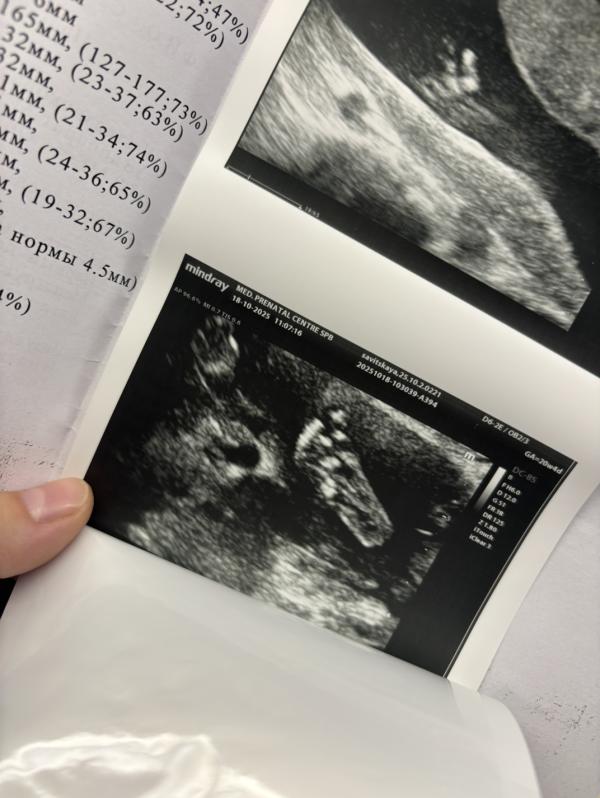

Сходила позавчера с мужем на 2 скрининг,сказали что с развитием все хорошо-но врач не смогла найти 3 фаланг мизинчика на кисти,и показала что на ножках большой пальцы оттопыренны (4 фото видео с узи-муж говорит все видно,а на ногах у тебя также оттопырен палец ),при 1 скрининге сдала кровь,низкие риски на 21 хромосому.

Порекомендовали сдать нипт,я уже накрутила себя .(1 скрининг делали платно-2 скрининг в этой же поликлинике сделали бесплатно через гинеколога)